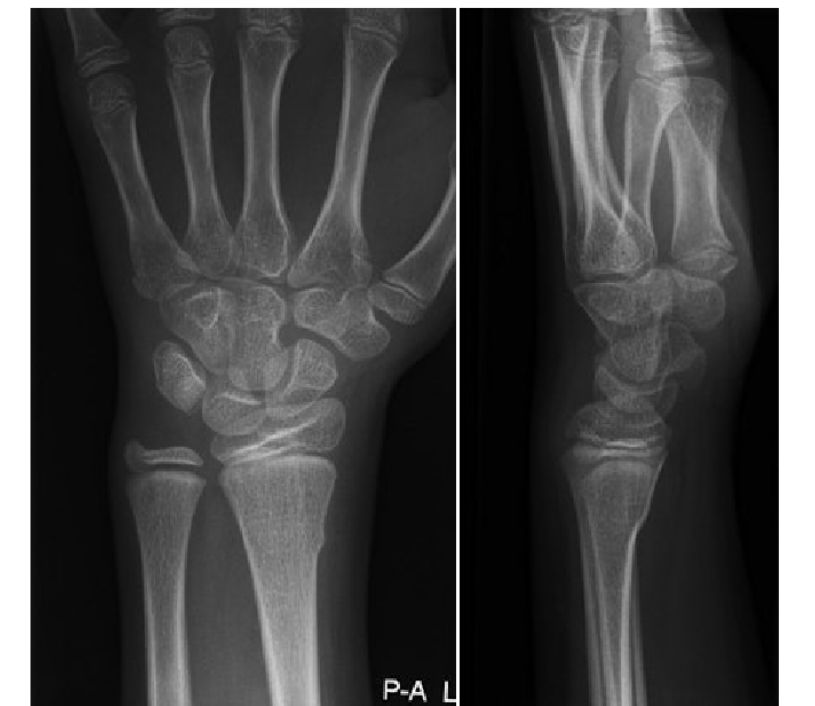

What is this?

Normal

Colles fracture